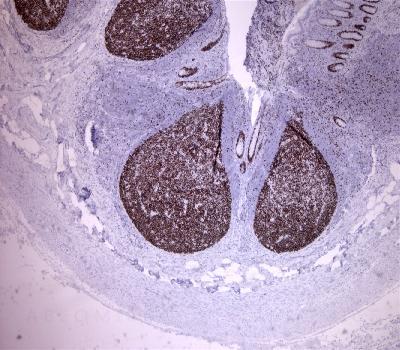

Figure-1: Appendix (4x) has been stained using mcm2 antibody (Clone: BS18).